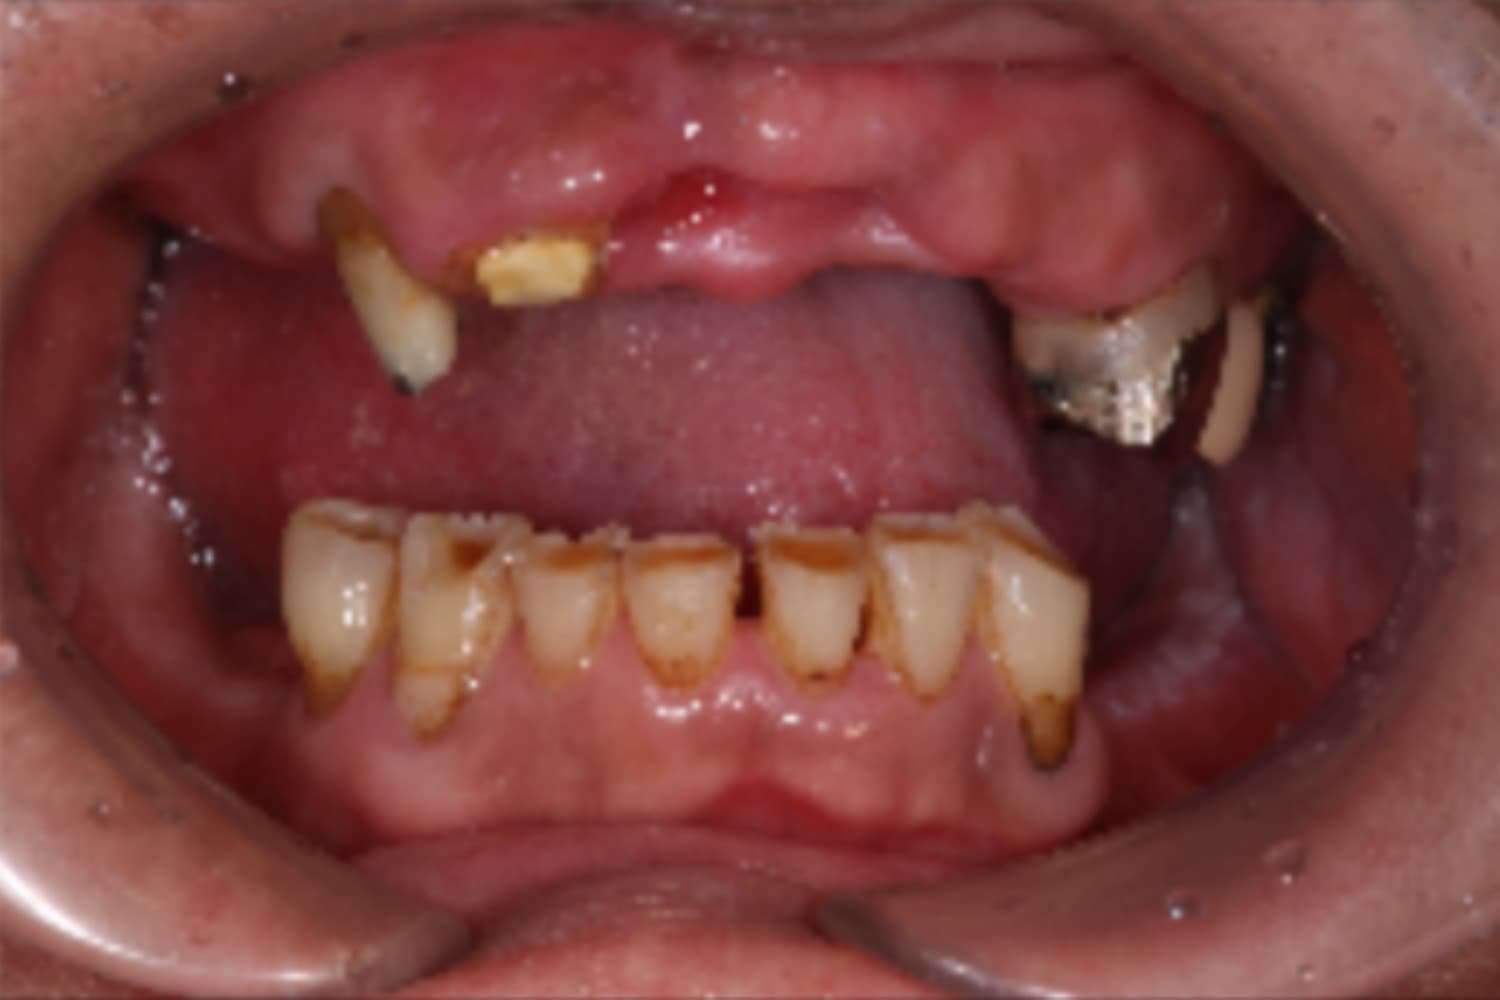

上顎すべてのインプラント治療

Before

After

上顎をインプラント7本で治療

主訴

上顎欠損部にインプラント治療希望

治療期間

18カ月

治療回数

26回

費用

3,450,000円

副作用・リスク

・噛み合わせの崩壊により、治療途中に顎の痛みや顎関節症様の発症リスクがあります。